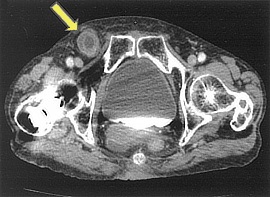

腹痛と嘔吐を主訴に精査加療目的に受診。CT検査にて、右鼡径部にヘルニア及び腸閉塞を認め、精査の結果、大腿ヘルニア嵌頓(かんとん)と診断。徒手整復を試みたが整復できず、手術(腹腔鏡下ヘルニア手術)を施行した。

CT画像